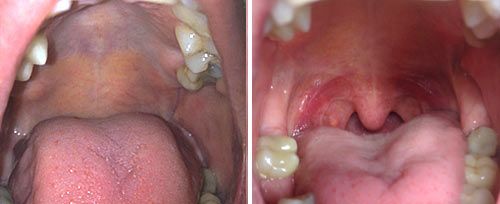

La terapia NightLase® de Fotona es un tratamiento láser no invasivo y amigable para el paciente que aumenta la calidad del sueño del paciente. NightLase® reduce los efectos de la apnea del sueño y disminuye la amplitud de los ronquidos por medio de un suave efecto de tensado inducido por el láser causando la contracción del colágeno en el tejido de la mucosa oral.

La modalidad de láser Er:YAG patentada por Fotona optimiza la  longitud de los pulsos láser, permitiendo la penetración segura de calor en el  tejido de la mucosa oral. Es lo suficientemente suave para ser utilizado en el  tejido sensible dentro de la boca, pero lo suficientemente fuerte como para  proporcionar un calentamiento clínicamente eficaz.